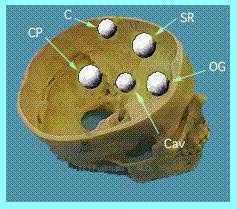

������̖���

������͗Տ��I�ɂ́i�]�O�Ȃ̎��ۂƂ��Ă͂�

�����Ӗ��j��ᇂ��ł��镔�ʂŕa��������킵

�܂��B���Ƃ��Α�]�~�W��������(C)�A��]��

������(F)�A�T�������(PS)�A���`������

����(SR)�A�C�ȐÖ�����������(Cav)�A���]��

�p��������(CP)�A�Α䕔������(CL)�A�ƌ��ߕ�

������(TS)�A�k�|��������(OG)�Ȃǂ̂悤�ɂ�

���܂��B�܂��]�̉��̂ق��ɂł�����̂�

���ē��W�ꕔ�̐�����Ƃ������Ƃ�����܂��B

�i�}�̗����Q�Ɓj